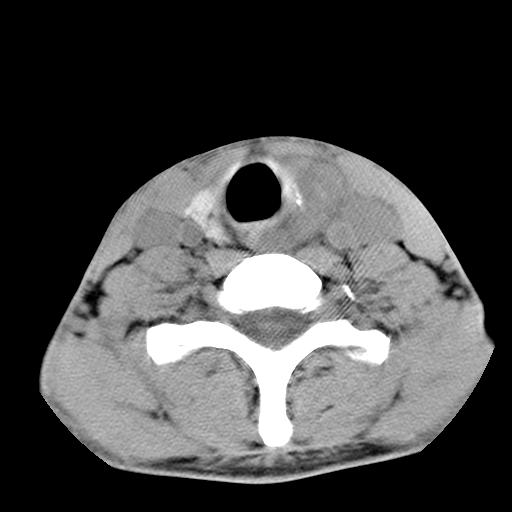

标题: CT15118:f-27y,左颈部肿一个月,无发热、无压痛 [打印本页]

标题: CT15118:f-27y,左颈部肿一个月,无发热、无压痛

1、甲状腺左叶病变:腺瘤?结节性增生?其他?

2、上极周围间隙病变。

3、2者关系?

左侧甲状腺肿大,密度不均.同侧甲状软骨似有破坏(建议传骨窗).左侧颈静脉增粗,各组织之间分界不清,有多个肿大淋巴结.甲状腺肿并感染?临床症状不符.淋巴结核?请结合其他检查.

结节性甲状腺肿

考虑结节性甲状腺肿;建议必要时行进一步检查。